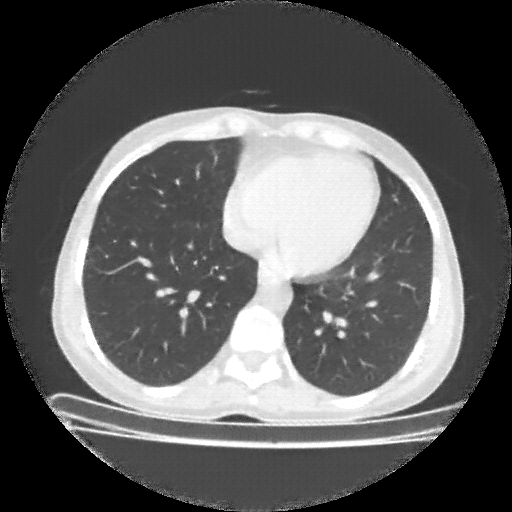

Image Grid

4×3 grid: Rows show different image types (Original NATIVE, Reconstructed NATIVE, Original VENOUS, Generated VENOUS), Columns show windowing techniques (No Window, Lung Window, Mediastinum Window)

Generated VENOUS CT scan (A→B translation)

Generated VENOUS CT scan (A→B translation)

Lung window (WL -600, WW 1500 → Low −1350, High +150)

Windowing Parameters

- No Window: Raw intensity values without windowing

- Lung Window: WL -600, WW 1500 → Low −1350, High +150 (optimal for pulmonary structures)

- Mediastinum Window: WL 40, WW 400 → Low −160, High +240 (optimal for soft tissues)